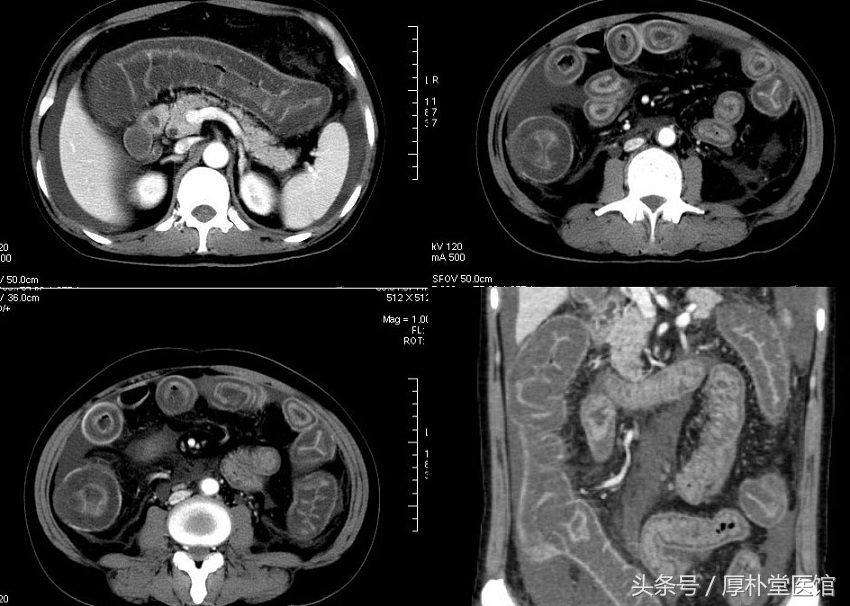

做了CT增强示肠管呈双环征

第三天结果出来了:抗核抗体 1:1000阳性、抗SSA和抗SSB均呈阳性。CT增强提示小肠肠壁呈典型的双环征,肠系膜呈筛状。风湿科会诊考虑自身免疫性肠炎。以干燥综合征可能性大。故安排了转科治疗。